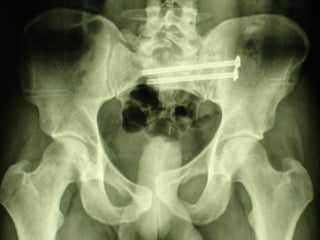

La lesione dell’apparato muscolo scheletrico che richiede  in ogni caso  un trattamento chirurgico con  priorità   assoluta  è la rottura dell’anello pelvico , che comporta una emorragia severa nel retro peritoneo e nella cavità peritoneale.

Immediata riduzione e fissazione del bacino

Se la risposta emodinamica a questo trattamento è buona il paziente verrà monitorato e potrà essere programmato un successivo intervento di osteosintesi definitiva

Angiografia e/o packing pelvico Se il paziente rimane instabile